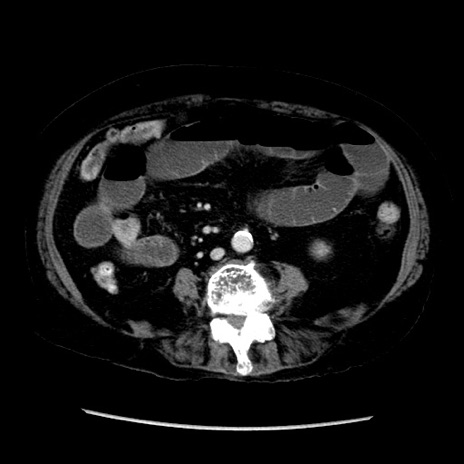

症例14(横断像)

【症例】 90歳代女性

【主訴】 腹痛・嘔吐

【現病歴】今朝から左側腹部痛を認めた。 経過観察していたが、嘔吐を認めたため来院。

【既往歴】 子宮癌術後

【身体所見】 意識清明、BP 127/54mmHg、P 98bpm Sp02 95%(RA)、BT 35.8°C、腹部平坦・軟腸ぜん動音聴取良好、右下腹部圧痛(+) 反跳痛なし

【データ】WBC 9800、CRP 0.46

冠状断像